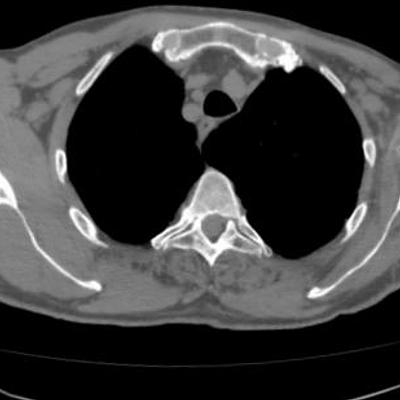

Purpose Segmentation of rheumatoid joints from CT images is a complicated task. The pathological state of the joint results in a non-uniform density of the bone tissue, with holes and irregularities complicating the segmentation process. For the specific case of the shoulder joint, existing segmentation techniques often fail and lead to poor results. This paper describes a novel method for the segmentation of these joints. Methods Given a rough surface model of the shoulder, a loop that encircles the joint is extracted by calculating the minimum curvature of the surface model. The intersection points of this loop with the separate CT-slices are connected by means of a path search algorithm. Inaccurate sections are correct ed by iteratively applying a Hough transform to the segmentation result. Results As a qualitative measure we calculated the Dice coefficient and Hausdorff distances of the automatic segmentations and expert manual segmentations of CT-scans of ten severely deteriorated shoulder joints. For the humerus and scapula the median Dice coefficient was 98. 9% with an interquartile range (IQR) of 95 .8% -99. 4% and 98. 5% (IQR 98 . 3% - 99. 2%) respectively. The median Hausdorff distances were 3.06 mm (IQR 2.30 mm - 4.14 mm) and 3.92 mm (IQR 1.96 mm - 5.92 mm) respectively.